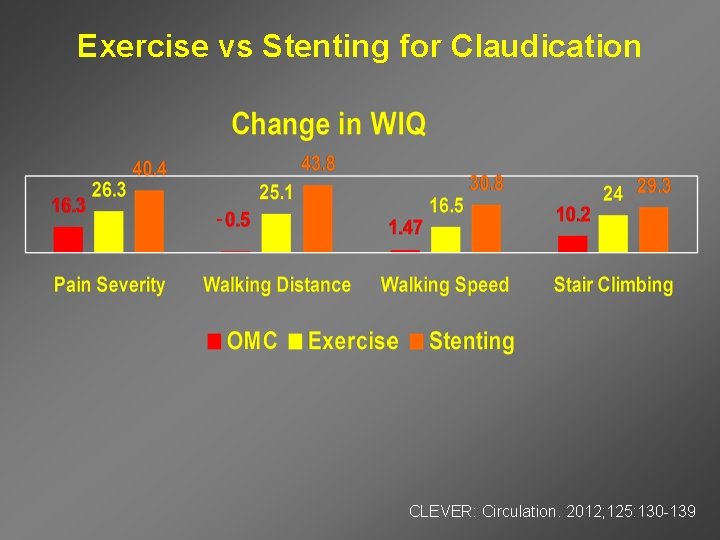

Exercise vs Stenting for Claudication - CLEVER: Circulation. 2012; 125: 130 -139